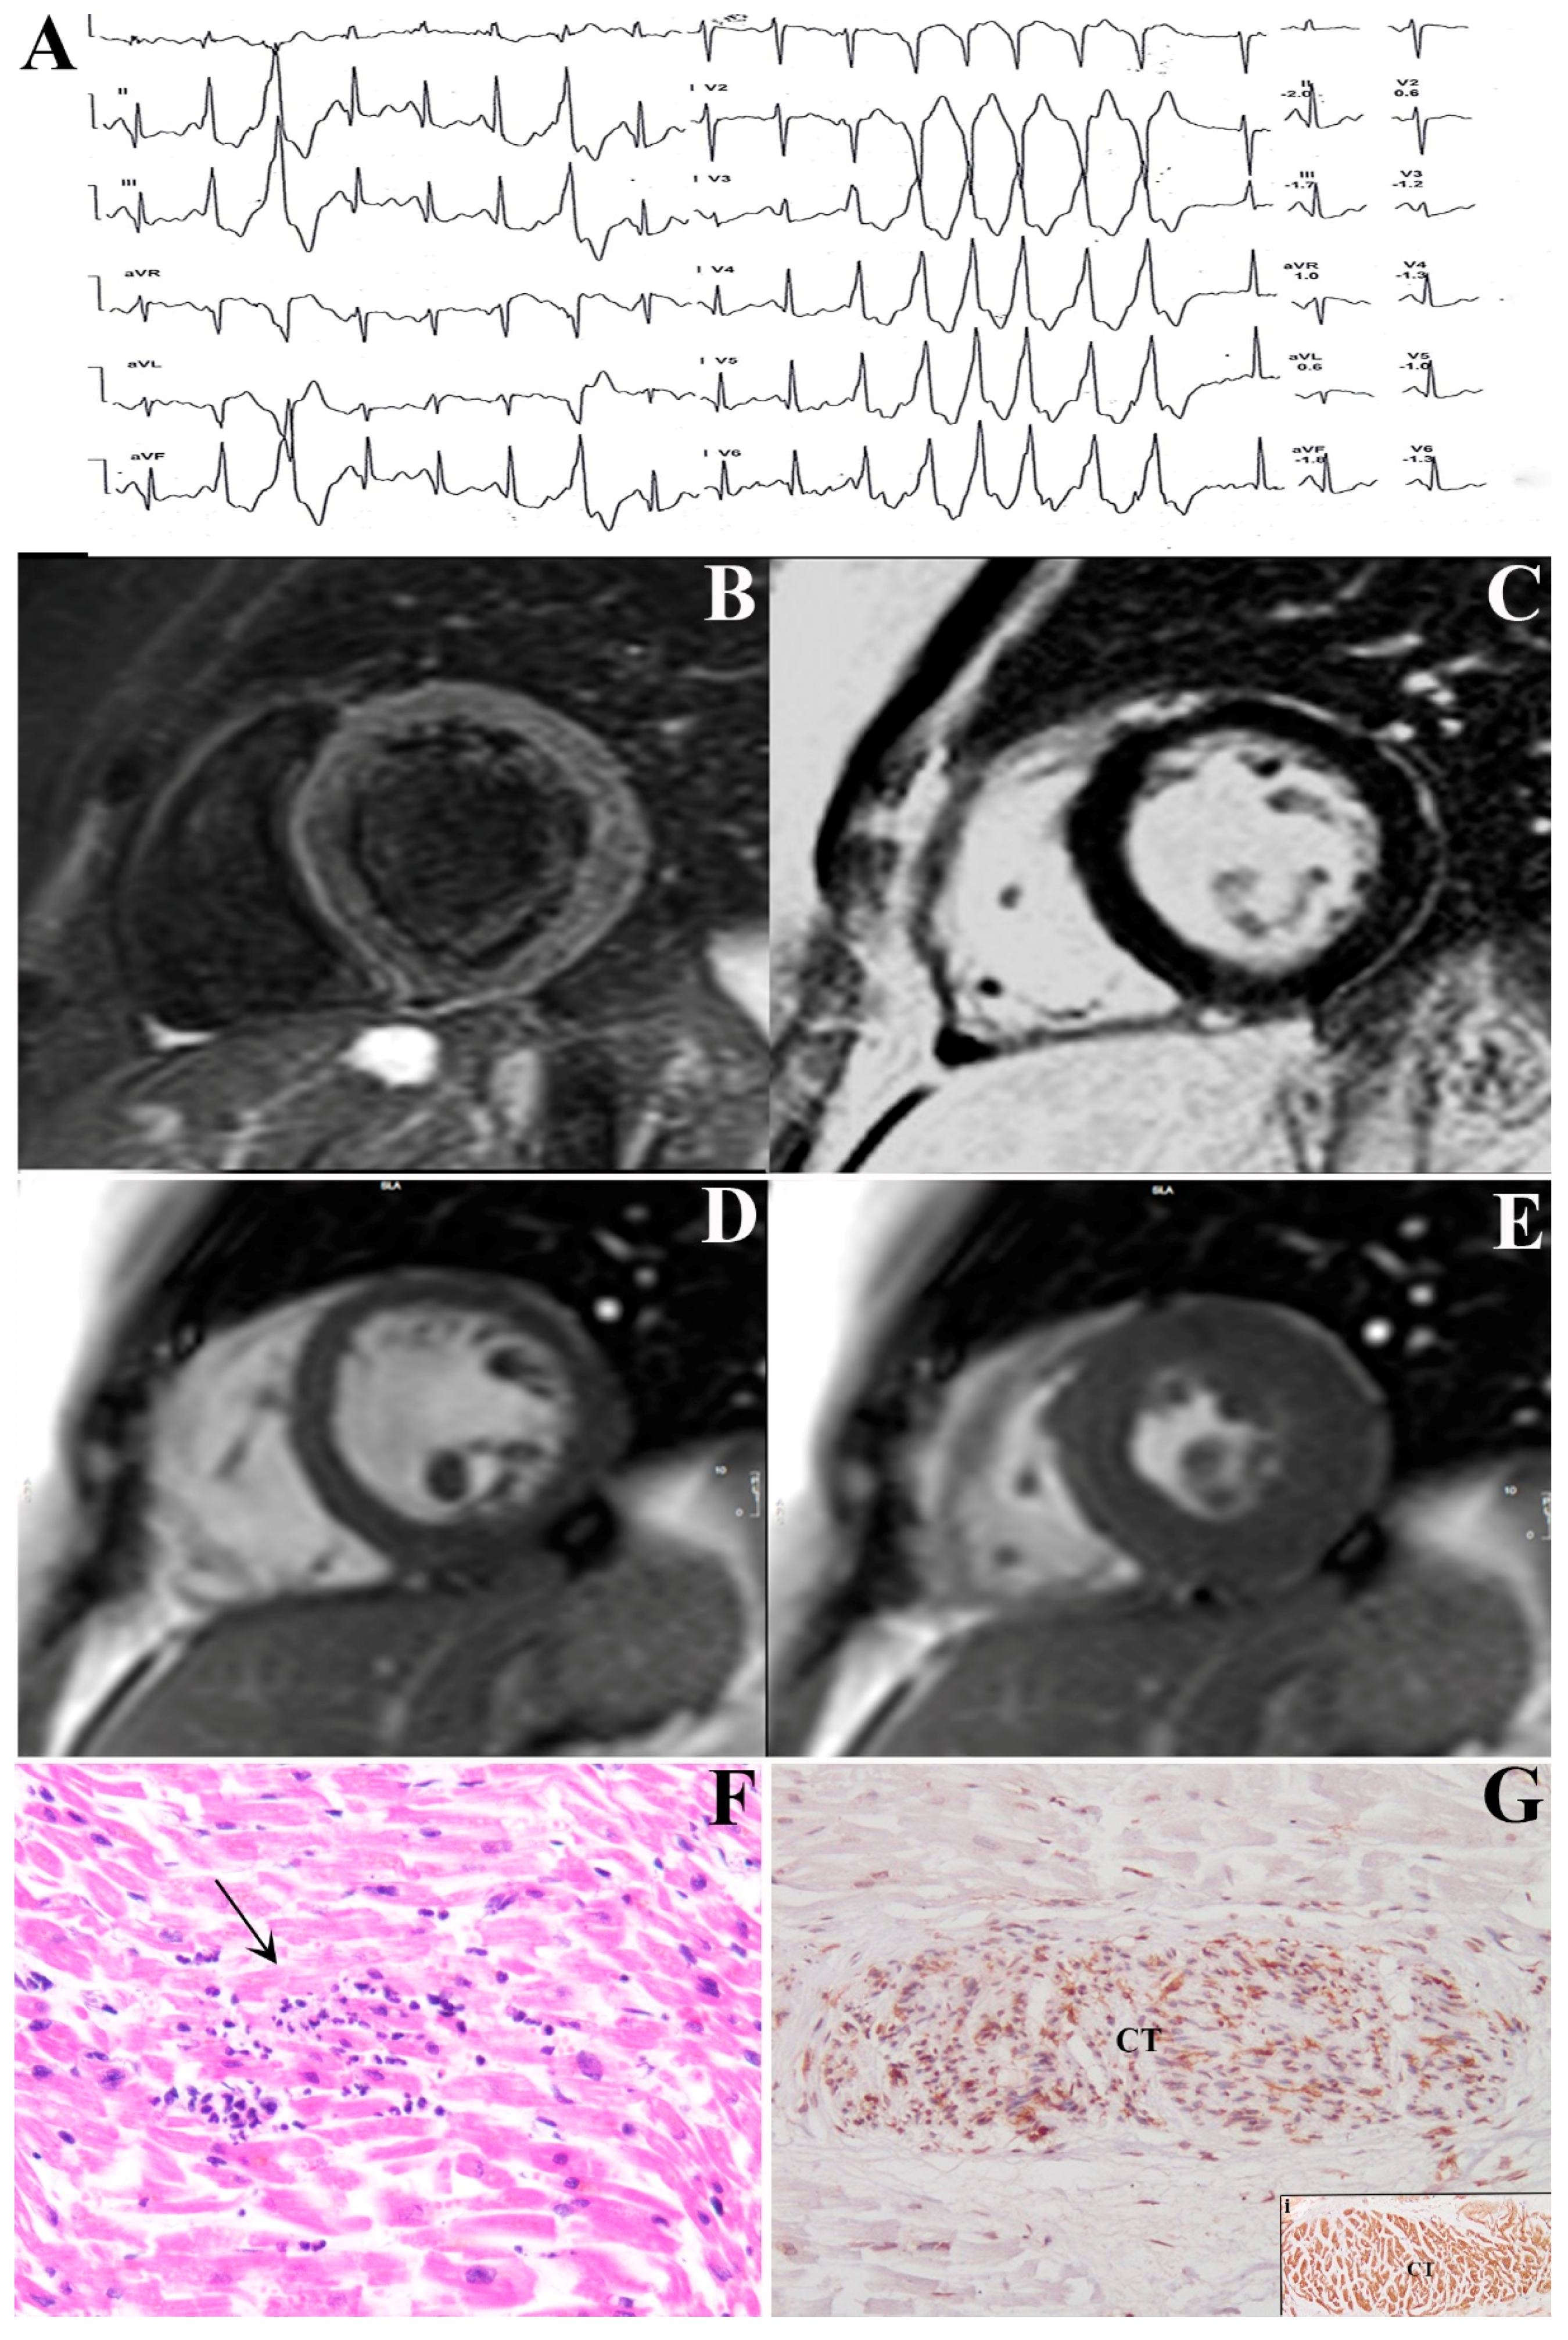

4.1. Clinical Studies

4.2. Endomyocardial Biopsy Studies